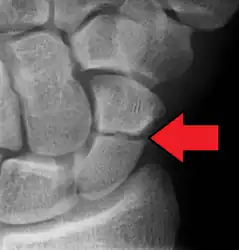

A subtle scaphoid fracture

Radiolucency around a 12 days old scaphoid fracture that was initially barely visible.[11]